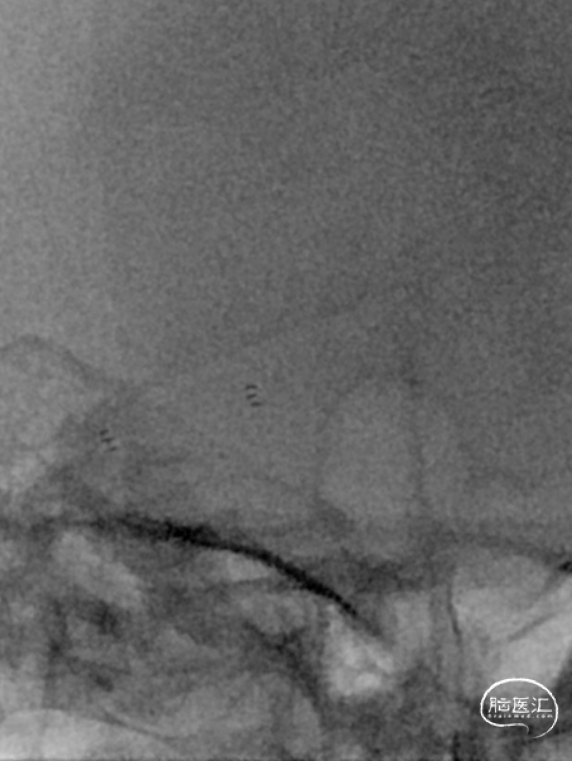

将Synchro(0.014×300cm)微导丝外衬Gateway(2.0×15mm)球囊缓慢通过RMCA M1段狭窄处,球囊定位于RMCA狭窄处缓慢扩张,压力6atm。采用交换技术置入灌注微导管,并将4.0×16mm支架定位于狭窄处释放。

复查造影见支架展开良好,支架内及远端血流通畅,TICI分级3级。术顺,术毕,Proglide缝合术口。